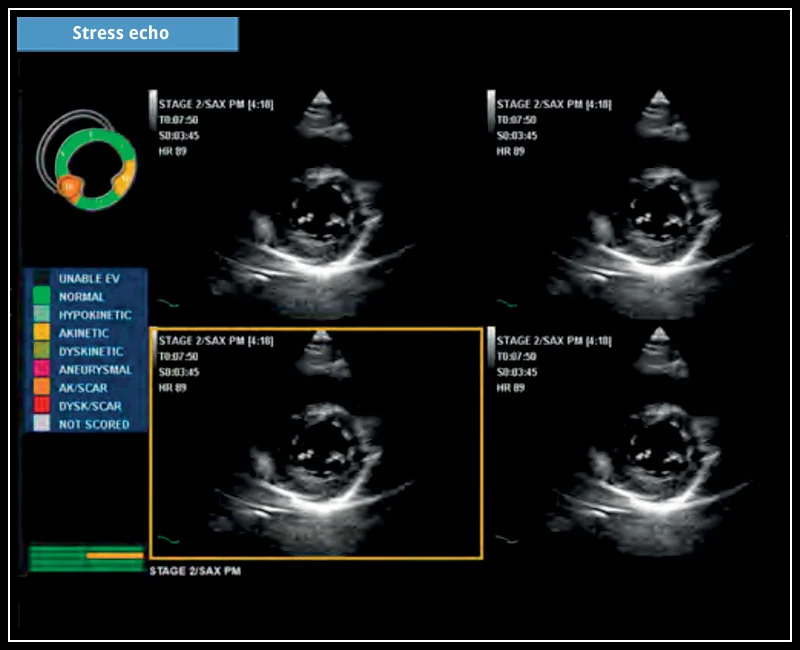

MyLab™X5 - Stress echo

MyLab™X5 - Stress echo